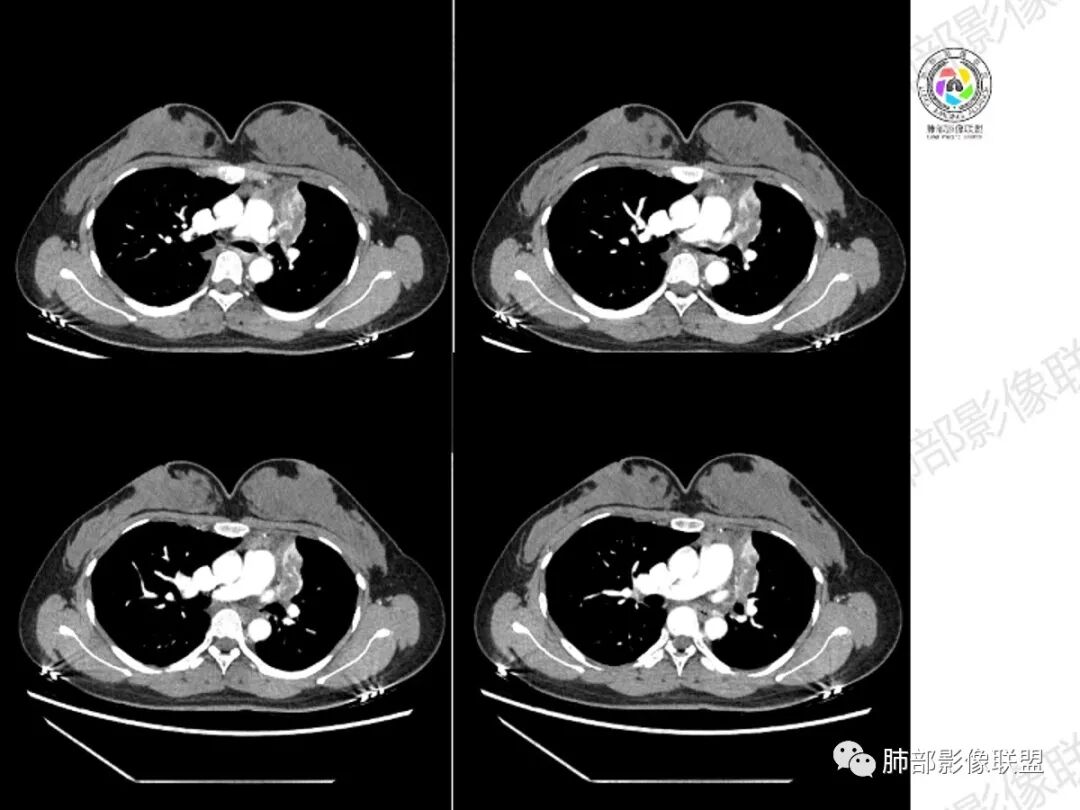

年轻女性,慢性病程,左上叶纵隔旁大片实变,心脏纵隔左移,左主及左上叶支气管变窄呈针孔样,实变内可见斑点状钙化,显著不均匀强化,内可见低密度粘液拴,显著强化不支持TB,左上叶不张在腺癌少见,综合病变部位及强化表现考虑粘液表皮样癌,其次考虑类癌

年轻女性,咳嗦咳痰伴咳血1月多,ct可见纵隔左移,左肺容积减小,左肺上叶可见一不规则实变影,朝肺内侧边界清楚,部分边缘与纵隔界限模糊,临近支气管堵塞,内见点状钙化,增强不均匀强化,内可见多个低密度区,粘液?并与左肺动脉界限模糊,似受侵,考虑恶性,黏表?但病灶远端有多发小结节,卫星灶?结核待排

胸部CT:左肺体积缩小,左肺上叶前段纵隔旁胸膜下大片实变影,边缘清楚、匀齐、平直收缩,部分略膨隆,周围多发结节、树芽卫星灶,纵隔窗病灶与纵隔胸膜黏连,实变内多发点状钙化。平扫密度尚均匀,增强扫描不均匀明显强化,多个低密度区,呈仙人掌样,伴有条状血管影,考虑慢性炎症伴左上叶前段支气管闭塞,TB?鉴别黏表、腺癌等。

青年女性、痰血症状一月,左胸廓缩小,左上肺固有段支气管狭窄堵塞,前段支气管扩张伴粘液栓、远侧肺不张,肿块整体呈梭形沿前段支气管爬行向外延伸,内可见多处圆形低密度坏死灶,肺不张处血管造影强化明显,周围散发束状细小结节灶,肺门及纵隔淋巴结尚正常。考虑结核可能大。

左上叶支气管堵塞,腔内粘液栓,粘液栓不强化,远端不张实变